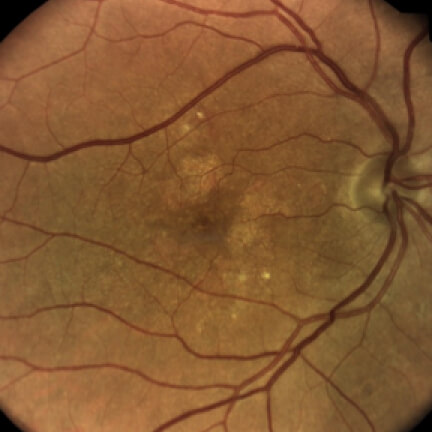

Color Fundus Photography (CFP)

Image courtesy of Dr. Mark Dunbar.

CFPCommonly used for a baseline, although small lesions may be difficult to distinguish3

Hypopigmented lesions are often circular and sharply demarcated with increased choroidal visibility.2